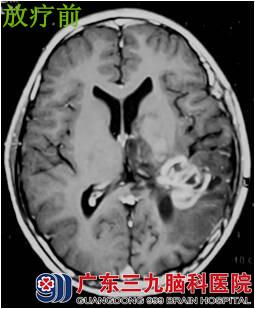

樊某,男性,14岁,1996年6月因“头痛伴恶心呕吐”外院行颅内肿瘤切除术,术后病理:星形细胞瘤Ⅱ级。术后出现发作性意识不清伴肢体抽搐,抗癫痫对症 ,1997年9月复查示肿瘤有复发迹象,遂到广东三九脑科医院肿瘤综合治疗中心进一步检查治疗。当时体征:神清,精神较差,言语欠流利,右上肢肌力Ⅳ级,右下肢肌力Ⅴ-级,右侧肢体肌张力稍高,腱反射亢进。行放射治疗后,残留肿瘤消失。1997至今服用抗癫痫药对症治疗,目前治疗已经17年,此次复查肿瘤无明显复发。